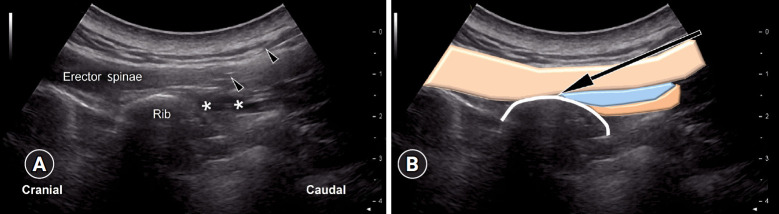

Myofascial pain syndrome (MPS) is a common musculoskeletal disorder characterized by muscle pain, tenderness, and trigger points. Ultrasonography has emerged as a key tool for diagnosing and treating MPS owing to its ability to provide precise, minimally invasive guidance. This review discusses the use of ultrasonography in various approaches to evaluate and manage MPS. Studies have shown that shear-wave sonoelastography can effectively assess muscle elasticity and offer insights into trapezius stiffness in patients with MPS. Ultrasound-guided interfascial hydrodissection, especially with visual feedback, has demonstrated effectiveness in treating trapezius MPS. Similarly, ultrasound-guided rhomboid interfascial plane blocks and perimysium dissection for posterior shoulder MPS have significantly reduced pain and improved quality of life. The combination of extracorporeal shockwave therapy with ultrasound-guided lidocaine injections has been particularly successful in reducing pain and stiffness in trapezius MPS. Research regarding various guided injections, including dry needling, interfascial plane blocks, and fascial hydrodissection, emphasizes the importance of ultrasonography for accuracy and safety. Additionally, ultrasound-guided delivery of local anesthetics and steroids to the quadratus lumborum muscle has shown lasting pain relief over a 6-month period. Overall, these findings highlight the pivotal role of ultrasonography in the assessment and treatment of MPS.